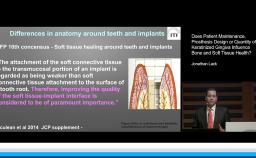

This presentation begins with a discussion of strategic extraction: whether teeth should be extracted as a first choice or kept as long as they function. An overview of estimated numbers of placed and failed implants internationally is given, and differences between the treatment strategies of prosthodontists, periodontists, general practitioners, and surgeons are presented. The definition, prevalence, and risk factors of peri-implantitis and related problems are emphasized. Assessment and diagnosis of peri-implantitis, the importance of radiographic assessment, and evaluation of progressive bone loss are described. The main part of the presentation concentrates on viable treatment options such as antibacterial therapy and ultrasonic debridement, highlighting that prevention is the best treatment.

- discuss prevalence and risk factors for peri-implantitis